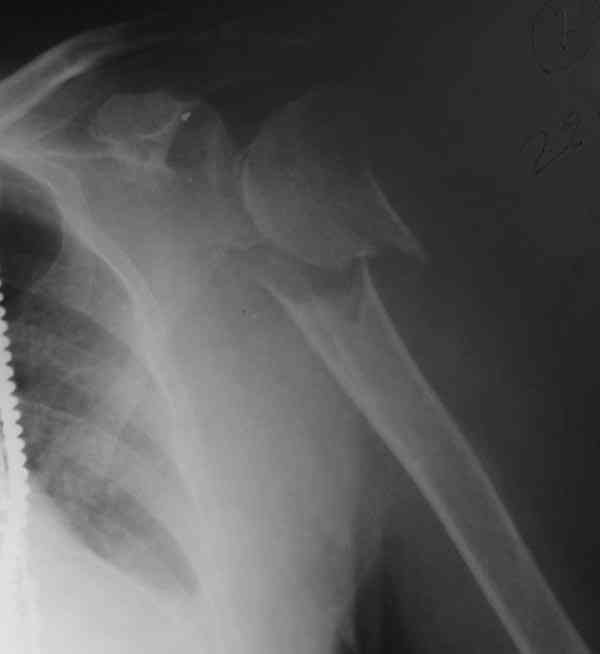

[Ortho] Comminuted fracture proximal humerus

The fracture is completely displaced in the axial view. It is probably

possible to align it with the patient in the vertical position, i.e.

sitting or standing. However, I would use a locking plate for the

tremendous pain relief it offers.

I am attaching the radiographs of the mother of a doctor. She has

chronic renal failure for >10 years, diabetes mellitus and coronary

artery disease. Age 62. She was offered the options of non-surgical

management in a sling and surgery with a locking plate. She was given

Tramadol for pain relief. Five days after injury, patient requested

surgery, because of pain, inability to move without pain.